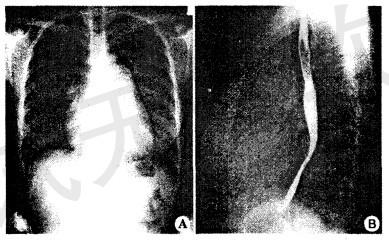

问题 女性,48岁。5年来渐进性劳累后心悸、气短,1年来加重,曾有夜间憋醒,需坐起后缓解,既往有关节痛史。检查发现心脏扩大,可闻及杂音,胸片显示如下。 该患者最可能的心脏病变是

选项 A.扩张型心肌病 B.风湿性心脏病 C.冠状动脉性心脏病 D.先天性心脏病

答案 B